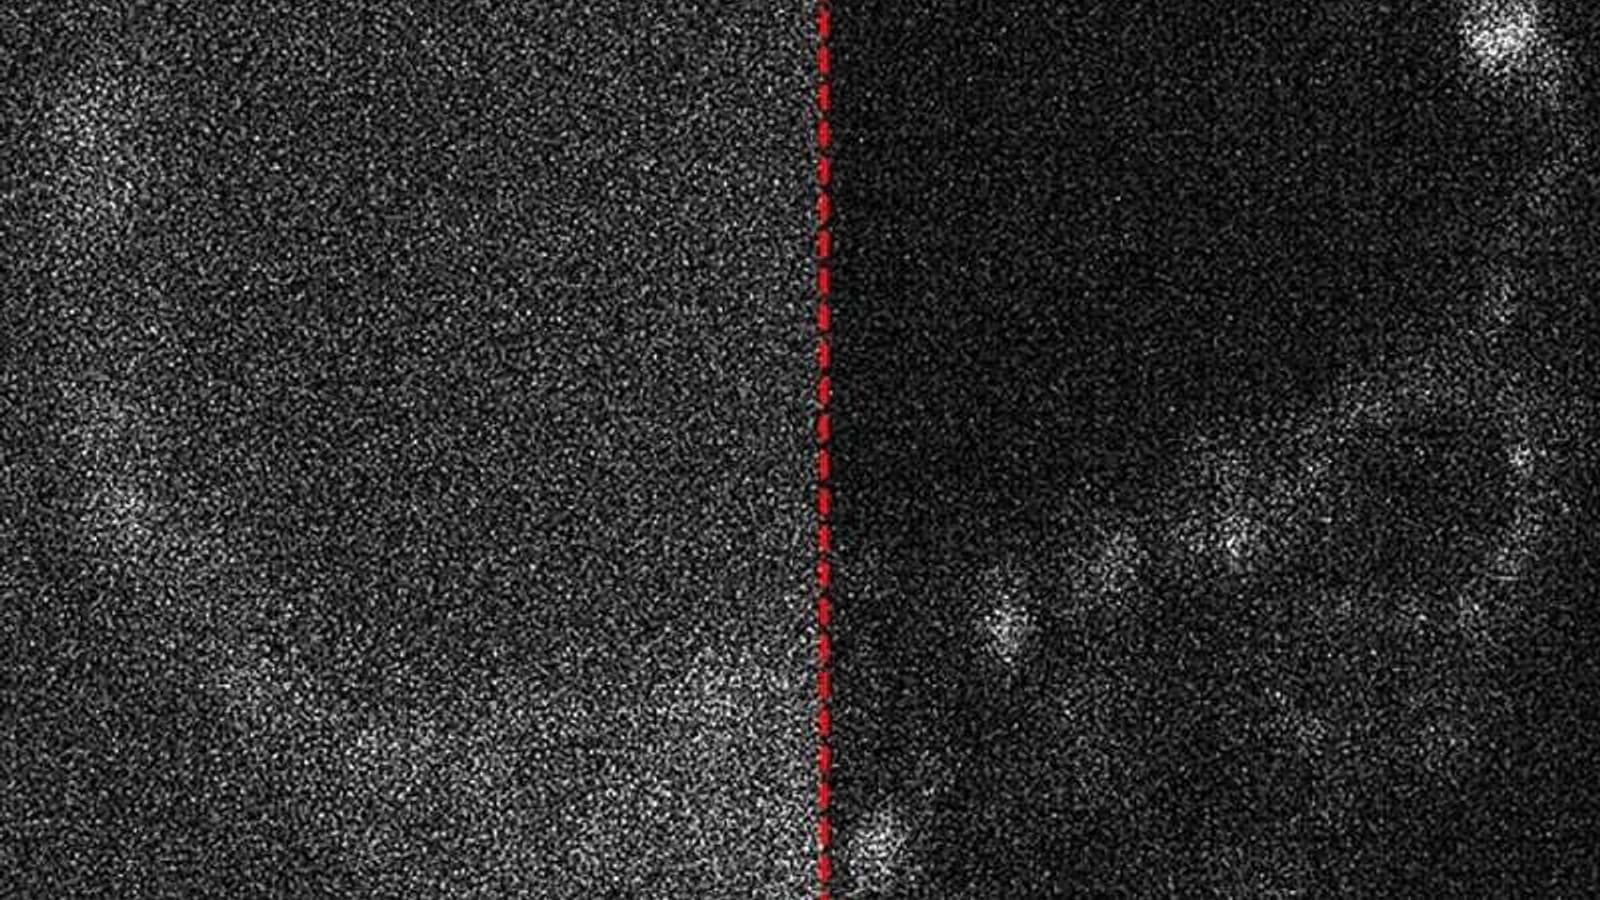

Анализ изображений стал возможен благодаря сочетанию экспертизы в области оптики, биологии, лазерной физики и микроскопии. Исследователи также изучили возможности использования искусственного интеллекта для удаления шумов с полученных изображений, которые возникают из-за недостаточного количества света при съёмке.